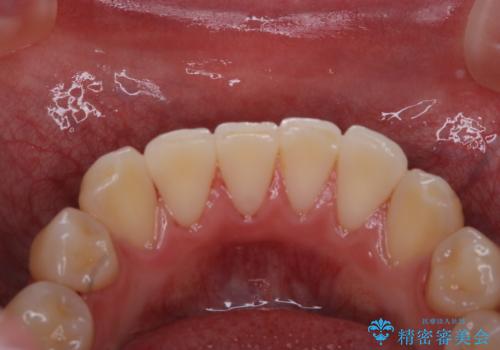

歯垢染色液を使うと、一見きれいな歯でも染まっている所が全て歯垢(プラーク)なのがはっきり分かります。歯に付着した歯垢(プラーク)は肉眼では認識しにくいものです。完璧に磨けているつもりでも、磨き残しが残っているかもしれません。

毎日の歯磨きだけでは、隅々までキレイに磨くことは困難です。さらに、体調不良や疲労などで免疫が低下しているとお口の中の細菌が増えやくなることがあります。

そのため、歯科医院にて定期的に歯磨きのチェックや専門的な機械でのクリーニングをすることが大切です。